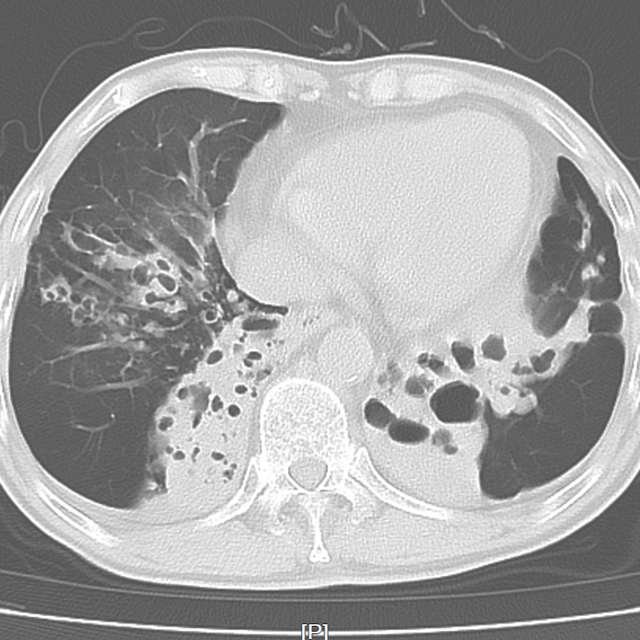

近日,外一科就收治了这样一位呼吸科的老病号,两个月前,老姚(化名)刚于呼吸科出院,出院诊断:支气管扩张伴感染、慢性支气管炎、肺气肿,痰培养为铜绿假单胞杆菌。

此次因胆囊结石伴胆囊炎、胆总管结石收治入院,其实患者的胆结石也是他的“老难题”了,前些年就想积极手术,奈何肺功能太差,辗转几次无果。除了手术本身的风险以外,围手术期心肺意外的风险很大,很有可能手术后气管插管拔管困难,需进ICU呼吸机支持。术后也同样存在肺不张、肺部感染、心衰等并发症。

▲患者肺部CT

每个并发症对于患者来说都是难以承受的打击。但此次腹痛,若不积极手术,胆总管结石进一步发展为化脓性胆管炎,病情则有可能会危及生命!

考虑患者近阶段生活可自理,饮食正常,活动量尚可,肺部疾病相对稳定,对手术有相对禁忌。与患者的儿子交流沟通后,患方表充分理解并愿积极配合。